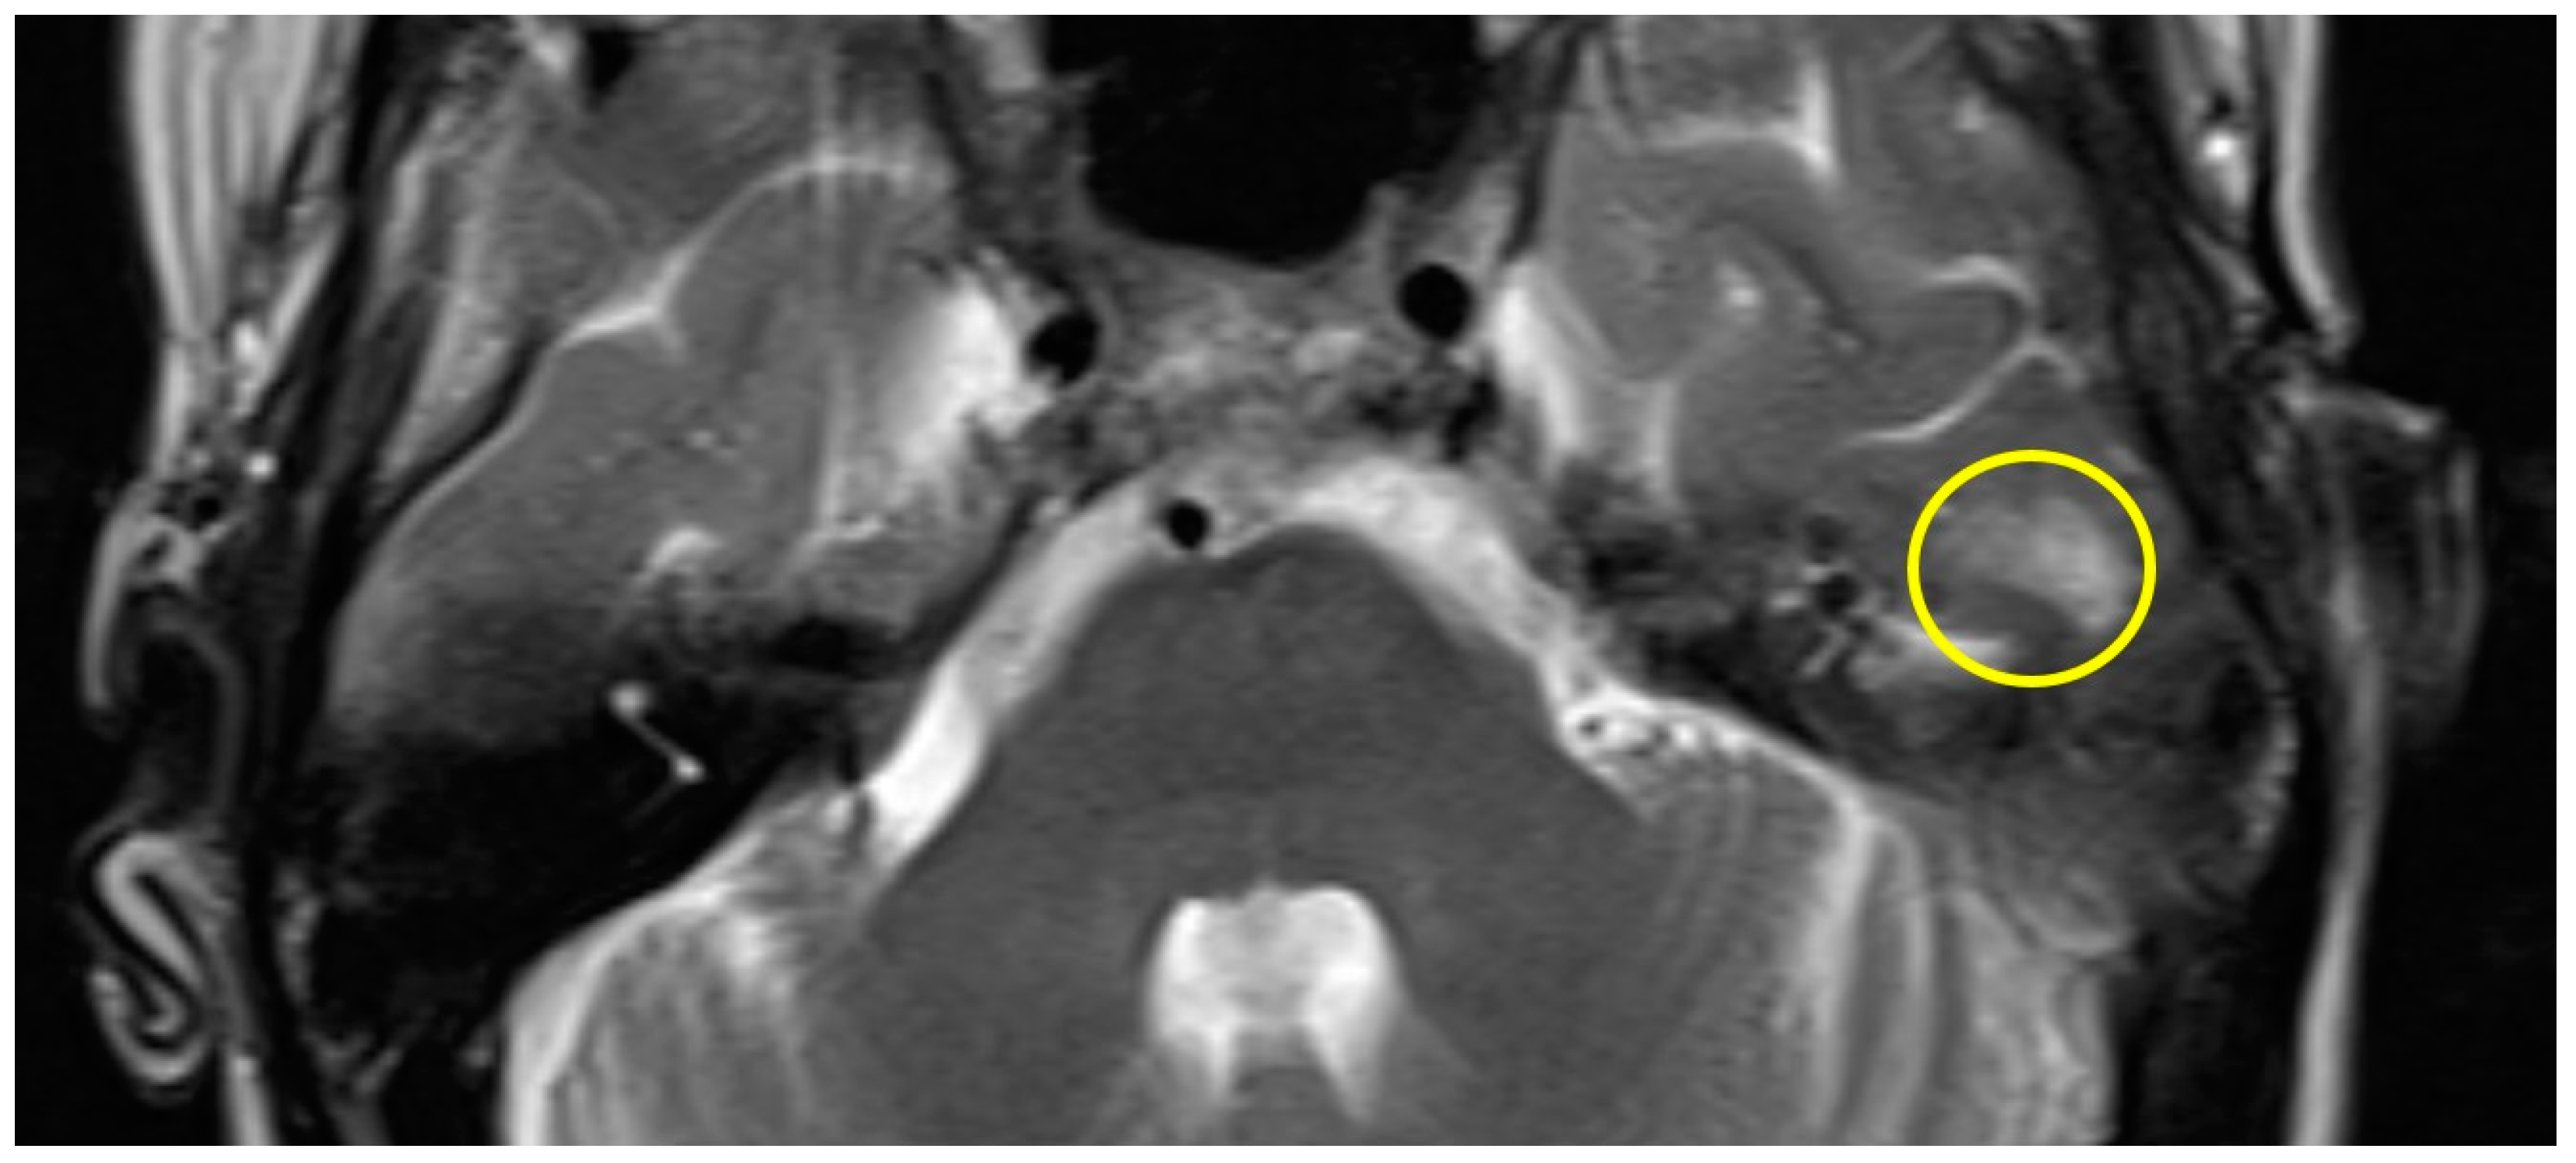

Patient #1 exhibited a slight gliosis on the left side during the follow-up MR 12 months postoperatively. On axial T2 weighted slides, a focal cortical and subcortical T2w signal increase was observed in the left temporal lobe (Figure 1). Patient #2 received early MR imaging only 3 months after surgery, which did not reveal any abnormalities. The subsequent second postoperative MR was conducted 16 months after surgery, revealing a slight gliosis of the right temporal lobe on the T2 axial images (Figure 2).

Figure 1.

Axial T2w MR imaging of patient #1 (yellow circle = gliosis). Supplementary MR imaging can be downloaded.